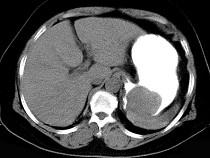

女43岁上腹不适多年,体检行CT扫描如图,最可能的诊断为()A.胃癌B.胃平滑肌瘤C.胃平滑肌肉瘤D.胃淋巴瘤E.胃蛔虫团块

问题 女43岁上腹不适多年,体检行CT扫描如图,最可能的诊断为()

选项 A.胃癌 B.胃平滑肌瘤 C.胃平滑肌肉瘤 D.胃淋巴瘤 E.胃蛔虫团块

答案 B